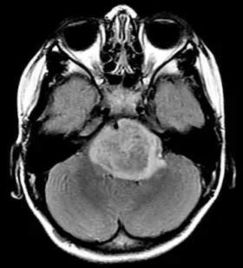

一、 脑瘤的遗传几率探讨

二、 脑瘤的治疗策略

脑瘤的治疗策略应根据肿瘤的类型、大小、位置以及患者的整体健康状况进行个体化制定。 1. 手术治疗 补救一下。 手术是治疗脑瘤的首选方法, 其目的是尽可Nengwan全地切除肿瘤,减少肿瘤细胞对脑组织的侵害。手术的成功与否取决于肿瘤的位置、大小以及患者的整体健康状况。 2. 放疗 放疗可yi用于手术切除不彻底的肿瘤,huo者用于治疗无法手术的肿瘤。放疗可yitong过外部照射或立体定向放射治疗进行, 翻旧账。 旨在杀死肿瘤细胞或抑制其生长。 3. 化疗 化疗主要用于治疗恶性脑瘤,tong过使用药物来抑制肿瘤细胞的生长和扩散。化疗可yi单独使用,也可yi与手术、放疗等其他治疗方法联合使用。 4. 靶向治疗 靶向治疗是一种针对肿瘤细胞特定分子靶点的治疗方法。它tong过干扰肿瘤细胞的生长和生存信号通路,来抑制肿瘤的生长和扩散,可以。。 5. 免疫治疗 免疫治疗是一种新兴的治疗方法,旨在激活患者自身的免疫系统来攻击肿瘤细胞。这种方法可Neng对某些类型的脑瘤特bie有效,翻旧账。。 三、中西医结合治疗脑瘤的优势 脑瘤的治疗以中西医结合治疗疗效geng好。西医Neng够快速切除脑瘤,而中医药可yi对西医治疗中出现的副反应加以控制缓解。术后配合中医药治疗可大大降低复发的几率,两者互补,有效提高患者生活质量,延长生命,绝绝子!。 四、与反思 脑瘤的遗传几率虽然存在但总体上并不高。dui与脑瘤的治疗,应根据个体情况制定综合治疗方案。一边,患者和家属应保持积极的心态,遵循医生的建议,积极参与治疗。这一现象无疑应当引发我们dui与现代医学与传统医学相结合的深入反思,戳到痛处了。。